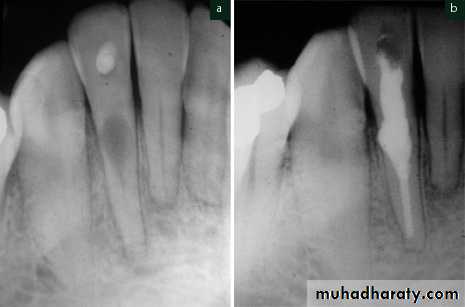

Internal root resorption

Internal resorption is initiated within the pulp cavity and results in loss of substance from dentinal tissue.Etiology

Exact etiology is unknown. Patient often presents with history of trauma, persistent chronic pulpitis, history of pulpotomy, crown preparation, force from orthodontic treatment, impacted teeth,…etc.

Symptoms

• Usually asymptomatic, recognized clinically through routine radiograph (especially in the root)• Pain occurs in cases of perforation of crown.

• “Pink Tooth” is the pathognomic feature of internal root resorption (especially in the crown).

Diagnosis

• Clinically:“Pink Tooth” appearance• Radiographic changes:

– Radiolucent enlargement of pulp canal

– Original root canal outline distorted

– Bone changes are seen only when root perforation into periodontal ligament takes place.

• Pulp tests: Positive, though coronal portion of pulp is necrotic, apical pulp could be vital

Treatment

• Pulp extirpation stops internal root resorption.

• Surgically treatment is indicated if conventional treatment fails.